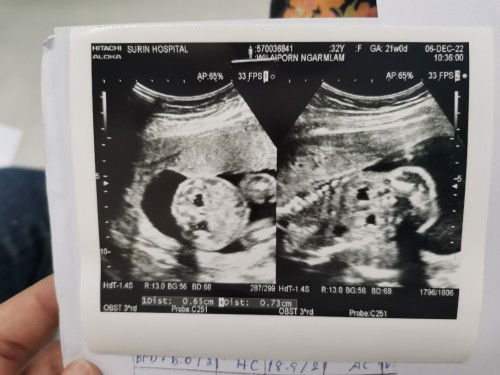

ตั้งครรภ์21วีค​ ตรวจเจอว่าน้องไตบวม

มีแม่ๆท่านไหนอัลตราซาวนด์​เจอว่าน้องในท้องไตบวมบ้างมั่ยคะ​ เจอตอน21วีค​ ได้เจาะน้ำคร่ำรอฟังผล​ 23​ ธันวานี้​ ตอนนี้เครียดมากๆเลยค่ะ